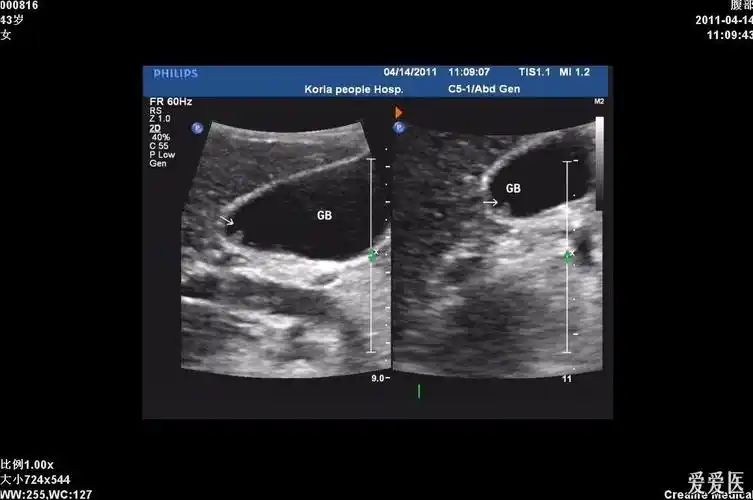

立竿见影精准排雷高危老年胆囊炎患者救治介入超声解难题